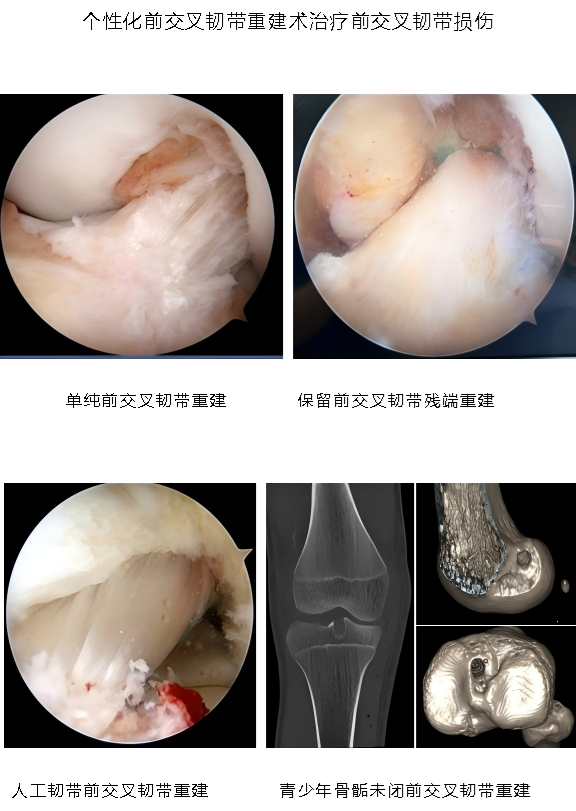

1.国际前沿的微创诊疗技术体系:科室聚焦肩、肘、髋、膝、踝多关节运动损伤,以 “精准化、个体化” 为核心,突破多项关键技术。膝关节领域:建立分龄化治疗方案 —— 青少年 “骨骺保护型前交叉韧带重建” 规避生长发育风险,成人 “联合前外侧韧带加强术” 提升术后稳定性,技术成熟度获行业广泛认可; 肩关节领域:个性化修复肩关节盂唇损伤、肩袖损伤,助力患者回归正常生活、重返运动;髋关节领域:为国内较早开展 “由外到内入路” 髋关节镜技术的科室之一,显著提升手术视野清晰度与操作安全性,年手术量超 300 台,居广东省前列。

3.核心业务范围:科室覆盖多关节运动损伤微创诊疗,主要包括:膝关节:前后交叉韧带重建、多韧带重建、半月板成形 / 修补 / 移植、髌股关节稳定术、关节软骨移植与修补、关节内游离体摘除;肩关节:肩袖撕裂关节镜下修补术、肩关节不稳关节镜下修复术(含 Laterjet 手术)、冻结肩关节镜下松解术、肩峰关节镜下减压成形术、SLAP 损伤修补术、肱二头肌腱固定术;髋关节:盂唇修补、股髋撞击症微创治疗、关节内游离体摘除;踝关节:踝关节不稳矫正、踝关节骨软骨损伤微创及开放治疗、跟腱腱病和断裂的微创及开放治疗、关节镜下各类踝关节疾病的微创治疗;肘关节:肘关节清理、网球肘、肘关节不稳、韧带重建;肘关节:腕关节清理、腕关节三角软骨损伤、腕关节不稳。